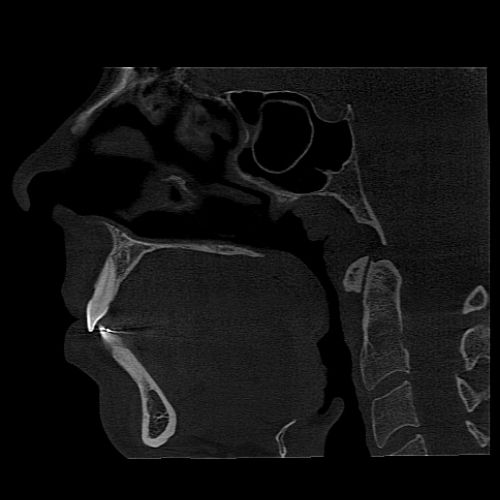

3D Algorithms: Enhancing Your Work-Flow Efficiency and Diagnostic Accuracy

UHD Mode for Endodontics

PreXion Excelsior MAX has a resolution with Isotropic Voxel of 75μm to 250μm.

Metal Artifact Reduction (MAR)

The PreXion Excelsior MAX line features three processing levels that can be chosen to correct gutta-percha deformities, implants and/or full arch prosthesis and metal restorations, in addition to automatic metal reduction. This tool also allows image reprocessing, for a better diagnosis, preventing the need to generate new exposure to the patient.